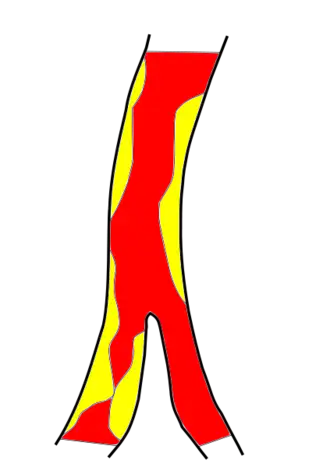

- атеросклероз и тромбообразование — наиболее распространённая патология церебральных и прецеребральных артерий, вызывающая ишемические нарушения мозгового кровообращения. Образование атеросклеротической бляшки обусловлено отложением липидов в стенке артерий. Рост атеросклеротической бляшки осложняется её изъязвлением и тромбообразованием вследствие адгезии тромбоцитов. Увеличение атеротромботической бляшки может привести к сужению просвета артерии и её полной закупорке; снижение кровотока возникает при гемодинамически значимом стенозе (сужение 70—75 % площади просвета) и далее нарастает пропорционально степени сужения. Фрагменты тромба и атеротромботической бляшки могут быть источником эмболии более дистального отдела артерии (артерио-артериальная эмболия). Исход атеросклеротического тромбоза или эмболии определяется скоростью его развития, локализацией закупорки, состоянием коллатерального кровообращения и активностью фибринолитической системы крови. При постепенном развитии атеросклероза формируется коллатеральное кровообращение, поэтому закупорка одной или даже нескольких прецеребральных артерий может не привести к локальной ишемии мозга и протекать бессимптомно. В случаях быстрого развития тромботической окклюзии или эмболии прецеребральной либо церебральной артерии возможности коллатерального кровообращения ограничены. В тех случаях, когда защитные механизмы не могут компенсировать сужение или закупорку артерии, развивается клинически значимая локальная ишемия мозга. Атеротромбоз и артерио-артериальная эмболия являются причиной до 50 % ишемических нарушений мозгового кровообращения[16]:232-233.

- гемодинамические ишемические нарушения мозгового кровообращения могут возникнуть при стенозе прецеребральных (чаще всего при стенозе сонных артерий) и (или) церебральных артерий, когда артериальное давление падает ниже нижней границы ауторегуляции мозгового кровообращения[16]:234. Дегенеративные и деформирующие изменения в шейном отделе позвоночника (остеохондроз позвоночника, деформирующий спондилёз, аномалии краниовертебральной области) могут приводить к сдавлению позвоночных или подключичных артерий извне с возможным развитием инсультов в вертебрально-базилярном бассейне[19] либо синдромов обкрадывания[16]:234.